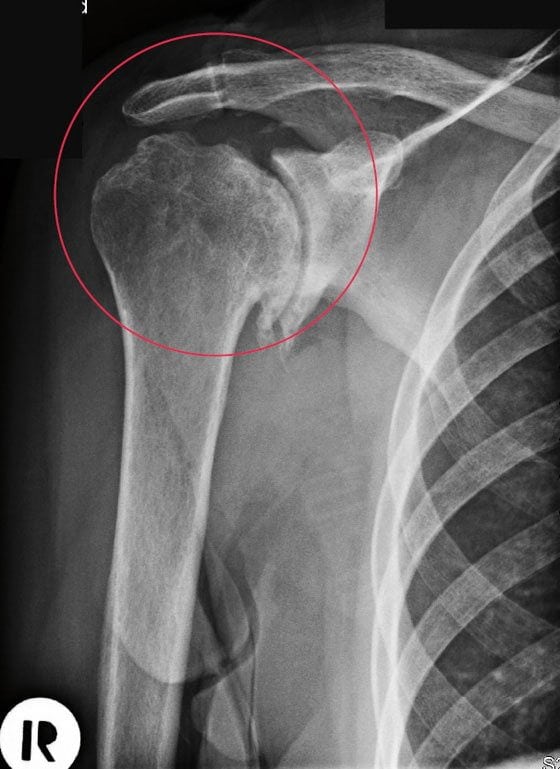

Артроз плечевого сустава — дегенеративно-дистрофическая патология, для которой характерно разрушение хрящей с последующей деформацией костных структур. Заболевание развивается из-за повышенных физических нагрузок, малоподвижного образа жизни, врожденных или приобретенных аномалий строения сочленения.

Спровоцировать артроз могут аутоиммунные патологии, например, системная красная волчанка, анкилозирующий спондилоартроз, ревматоидный артрит. Клинически заболевание проявляется следующими симптомами:

- болью в состоянии покоя, при сгибании и разгибании сустава, отведении и подъеме руки;

- утренней припухлостью и скованностью движений;

- хрустом, щелчками, треском, возникающими при любом движении плечом.

Если больной не обращается за медицинской помощью, то наблюдается снижение мышечной силы и чувствительности, выпадение рефлексов. Постепенно сращивается суставная щель, что приводит к полному или частичному обездвиживанию (анкилозу).